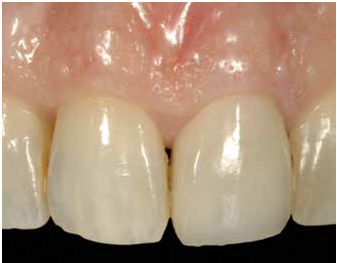

-軟組織區 (Fig 1,2)是指"植體與支台交界以上的區域" , 這個區域的組織若型態改變或變薄, 則內部的abutment將會透出顏色使組織變色 (abutment shine-through effect)

-硬組織區 (Fig 3,4)則是指"植體與支台交界以下的區域" , 這個區域的組織若因骨嵴塌陷造成型態改變或變薄, 則內部的implant body也可能會透出顏色使組織變色 (implant body shine-through effect)

(Fig 1,2)

(Fig 3,4)